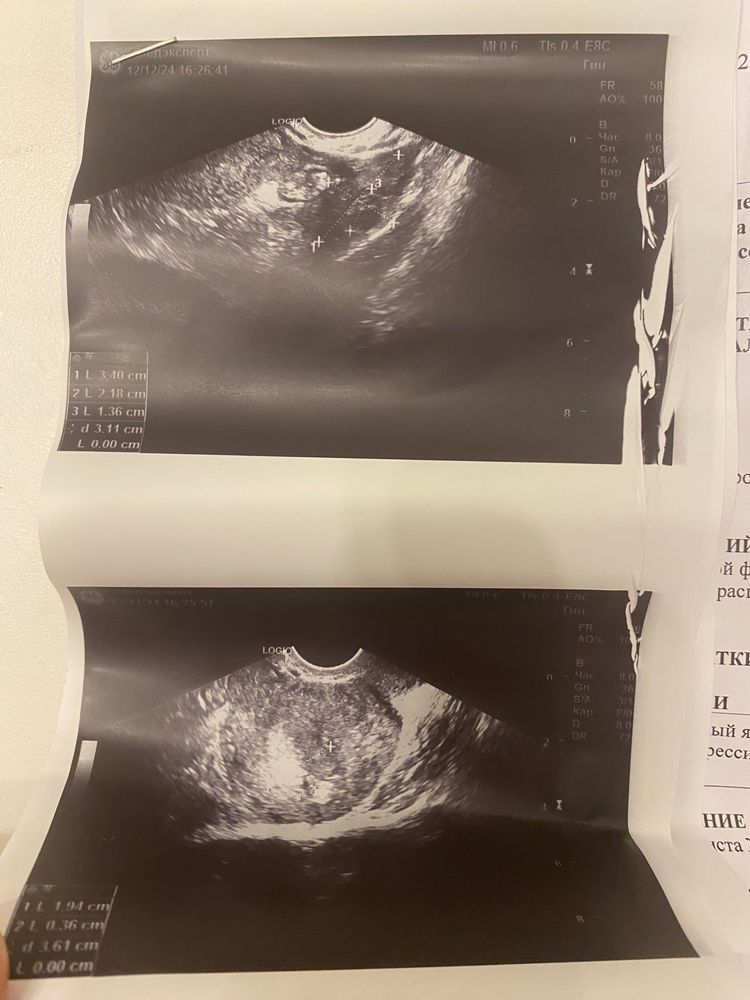

позавчера я сделала дешевые тесты с розочкой 4й на фото. Поняла, что все плохо. На утро сдала хгч 44.42. Что мало для моего срока.но, я подозреваю, что овуляция была поздняя 28.11.24. 5й тест на фото также сделан вчера. Грудь набухает и болит( УЗИ также делала позавчера.

На узи услышав сколько хгч, сразу сказала что это не беременность. Посмеялась, сказала вот вот пойдут месячные.